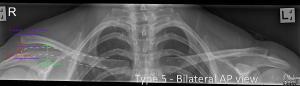

Grade V

The Clavicle is markedly elevated with coracoclavicular distance more than twice normal.

Comparative views can be useful if you are clinically suspicious of an ACJ injury, but normal AP views are not conclusive.